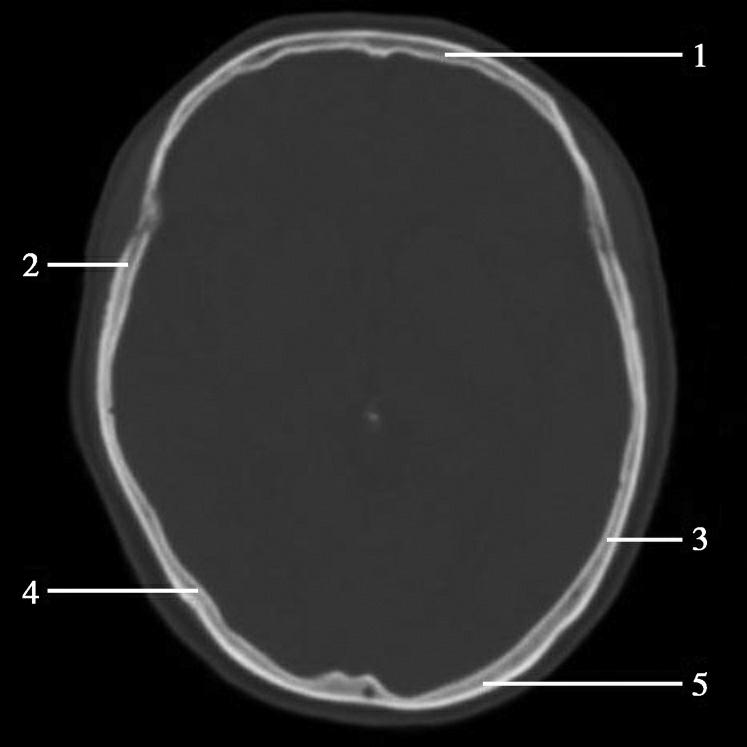

图1-2-2 颅底层面(骨窗)

A.横断面;B.横断面标注

1.鼻骨;2.筛窦纸板;3.颧骨眶突;4.翼腭窝;5.蝶骨大翼;6.卵圆孔;7.破裂孔;8.颞骨颧突;9.棘孔;10.斜坡;11.颞骨岩部;12.乳突;13.颈静脉孔;14.枕乳突缝;15.枕骨;16.枕内隆凸